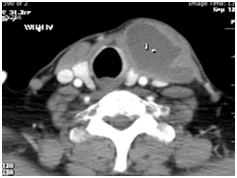

A 72-year-old man presented with history of left thyroid lobe swelling for 5-7month, which was gradually increasing in size with no compressive of neck structure or any associated symptoms. On physical examination, he had a left thyroid cystic and solid nodule.The nodule was no tender and moving with swallowing. Lymph node was not palpable in the neck. The systemic examination was normal, clinically he was euthyroid. Ultrasound of thyroid showed a left sided show cystic and solid nodule. CT-scan of neck with IV contrast shows a solid and cystic mass with peripheral vascularity. The right lobe was normal in size with few small solid and cystic nodules (Figure 5). Her chest X-ray was normal. His CRP, ESR and complete blood count and routine biochemistry were normal.FNA of left thyroid lobe in two time was performed which showed pus material. Cytology revealed follicular lesion. AFB in aspirated pus by Ziehl Nelsen stain was negative. Culture for bacterial and tuberculosis was negative too. He underwent left lobectomy and istmectomy, and her histopathology report showed granulomatous inflammation in the left lobe. With pathologic finding of chronic granulomatous inflammation along with necrosis and with possibility of tuberculosis in the left lobe (Figure 6), he was started on antituberclusis treatment with four drug regimen for the first 2months followed by three drugs regimen for the next 4months along with. He completed her treatment and in follow-up remained asymptomatic.T4, T3 and TSH was in normal range.

Figure 5 CT-scan of neck show a cystic lesion in thyroid.